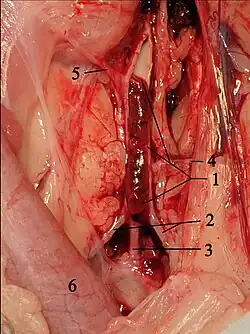

Bei Katzen entstehen die Blutgerinnsel vor allem im linken Herzohr.[9] Sie oder Teile von ihnen werden mit dem Blutstrom mitgerissen, gelangen über die linke Herzkammer in die Aorta, bleiben an Gefäßabgängen hängen und verstopfen diese. Dieser Zustand wird als Thromboembolie oder Thrombembolie bezeichnet. Bei Katzen tritt dies überwiegend in der Aorta im Bereich ihrer Endaufzweigung, also am Abgang der beiden äußeren Beckenarterien (Aa. iliacae externae), auf. Dies wird auch als „Sattelthrombus“ oder als „Reitender Thrombus“ bezeichnet. Dadurch kommt es zu einer Blutunterversorgung der hinteren Extremitäten. Zusätzlich werden durch die Blutplättchen Thromboxan und Serotonin freigesetzt, welches zu einer Gefäßverengung und damit zu einer Minderdurchblutung auch nicht direkt betroffener Blutgefäße führt. Serotonin stimuliert darüber hinaus Schmerzfasern, was zu der hohen Schmerzhaftigkeit der Erkrankung beiträgt.[10] Nur in 10 % der Fälle sind andere Blutgefäße betroffen, beispielsweise die Oberarmarterie, die Lungenarterien, Hirngefäße, Darmgefäße oder Herzkranzgefäße.[11][12]

Die naheliegende Behandlung, die Wiedereröffnung des Gefäßes durch medikamentöse Auflösung (Thrombolyse) oder invasive Entfernung des Gerinnsels (Thrombektomie), wie sie in der Humanmedizin bei Verschlusskrankheiten wie Schlaganfall oder Herzinfarkt lange etabliert ist, liefert bei Katzen unbefriedigende Ergebnisse und wird daher nicht mehr empfohlen.[33] Die Thrombolyse mit Streptokinase, Urokinase oder Gewebespezifischem Plasminogenaktivator hat in verschiedenen Studien keine Verbesserung des Behandlungserfolgs erbracht. Hierbei kommt es meist zu häufig tödlich verlaufenden Reperfusionstörungen, Hyperkaliämie, metabolischer Azidose, Nierenversagen und Blutungen, so dass die Überlebensrate häufig geringer ist als mit konservativer Behandlung.[47][48] Solche Behandlungen werden in der Humanmedizin nur in hochspezialisierten Einrichtungen (Herzzentren, Stroke Units) mit hohem personellen und apparativen Aufwand durchgeführt. In der neueren Literatur gibt es jedoch Hinweise, dass Alteplase und Reteplase die Rekanalisation fördern.[4] Die chirurgische Beseitigung des Thrombus wird in der Tiermedizin aufgrund der damit verbundenen Risiken ebenfalls selten durchgeführt, obwohl sie in Einzelfällen erfolgreich sein kann.[49] Sie ist mit den gleichen Komplikationen vergesellschaftet wie die Thrombolyse und wird deshalb nicht mehr empfohlen. Daher wird gegenwärtig auf die körpereigene Auflösung des Gerinnsels und damit auf die spontane Rekanalisation gesetzt, die in knapp 40 % der Fälle schnell genug eintritt.[47]